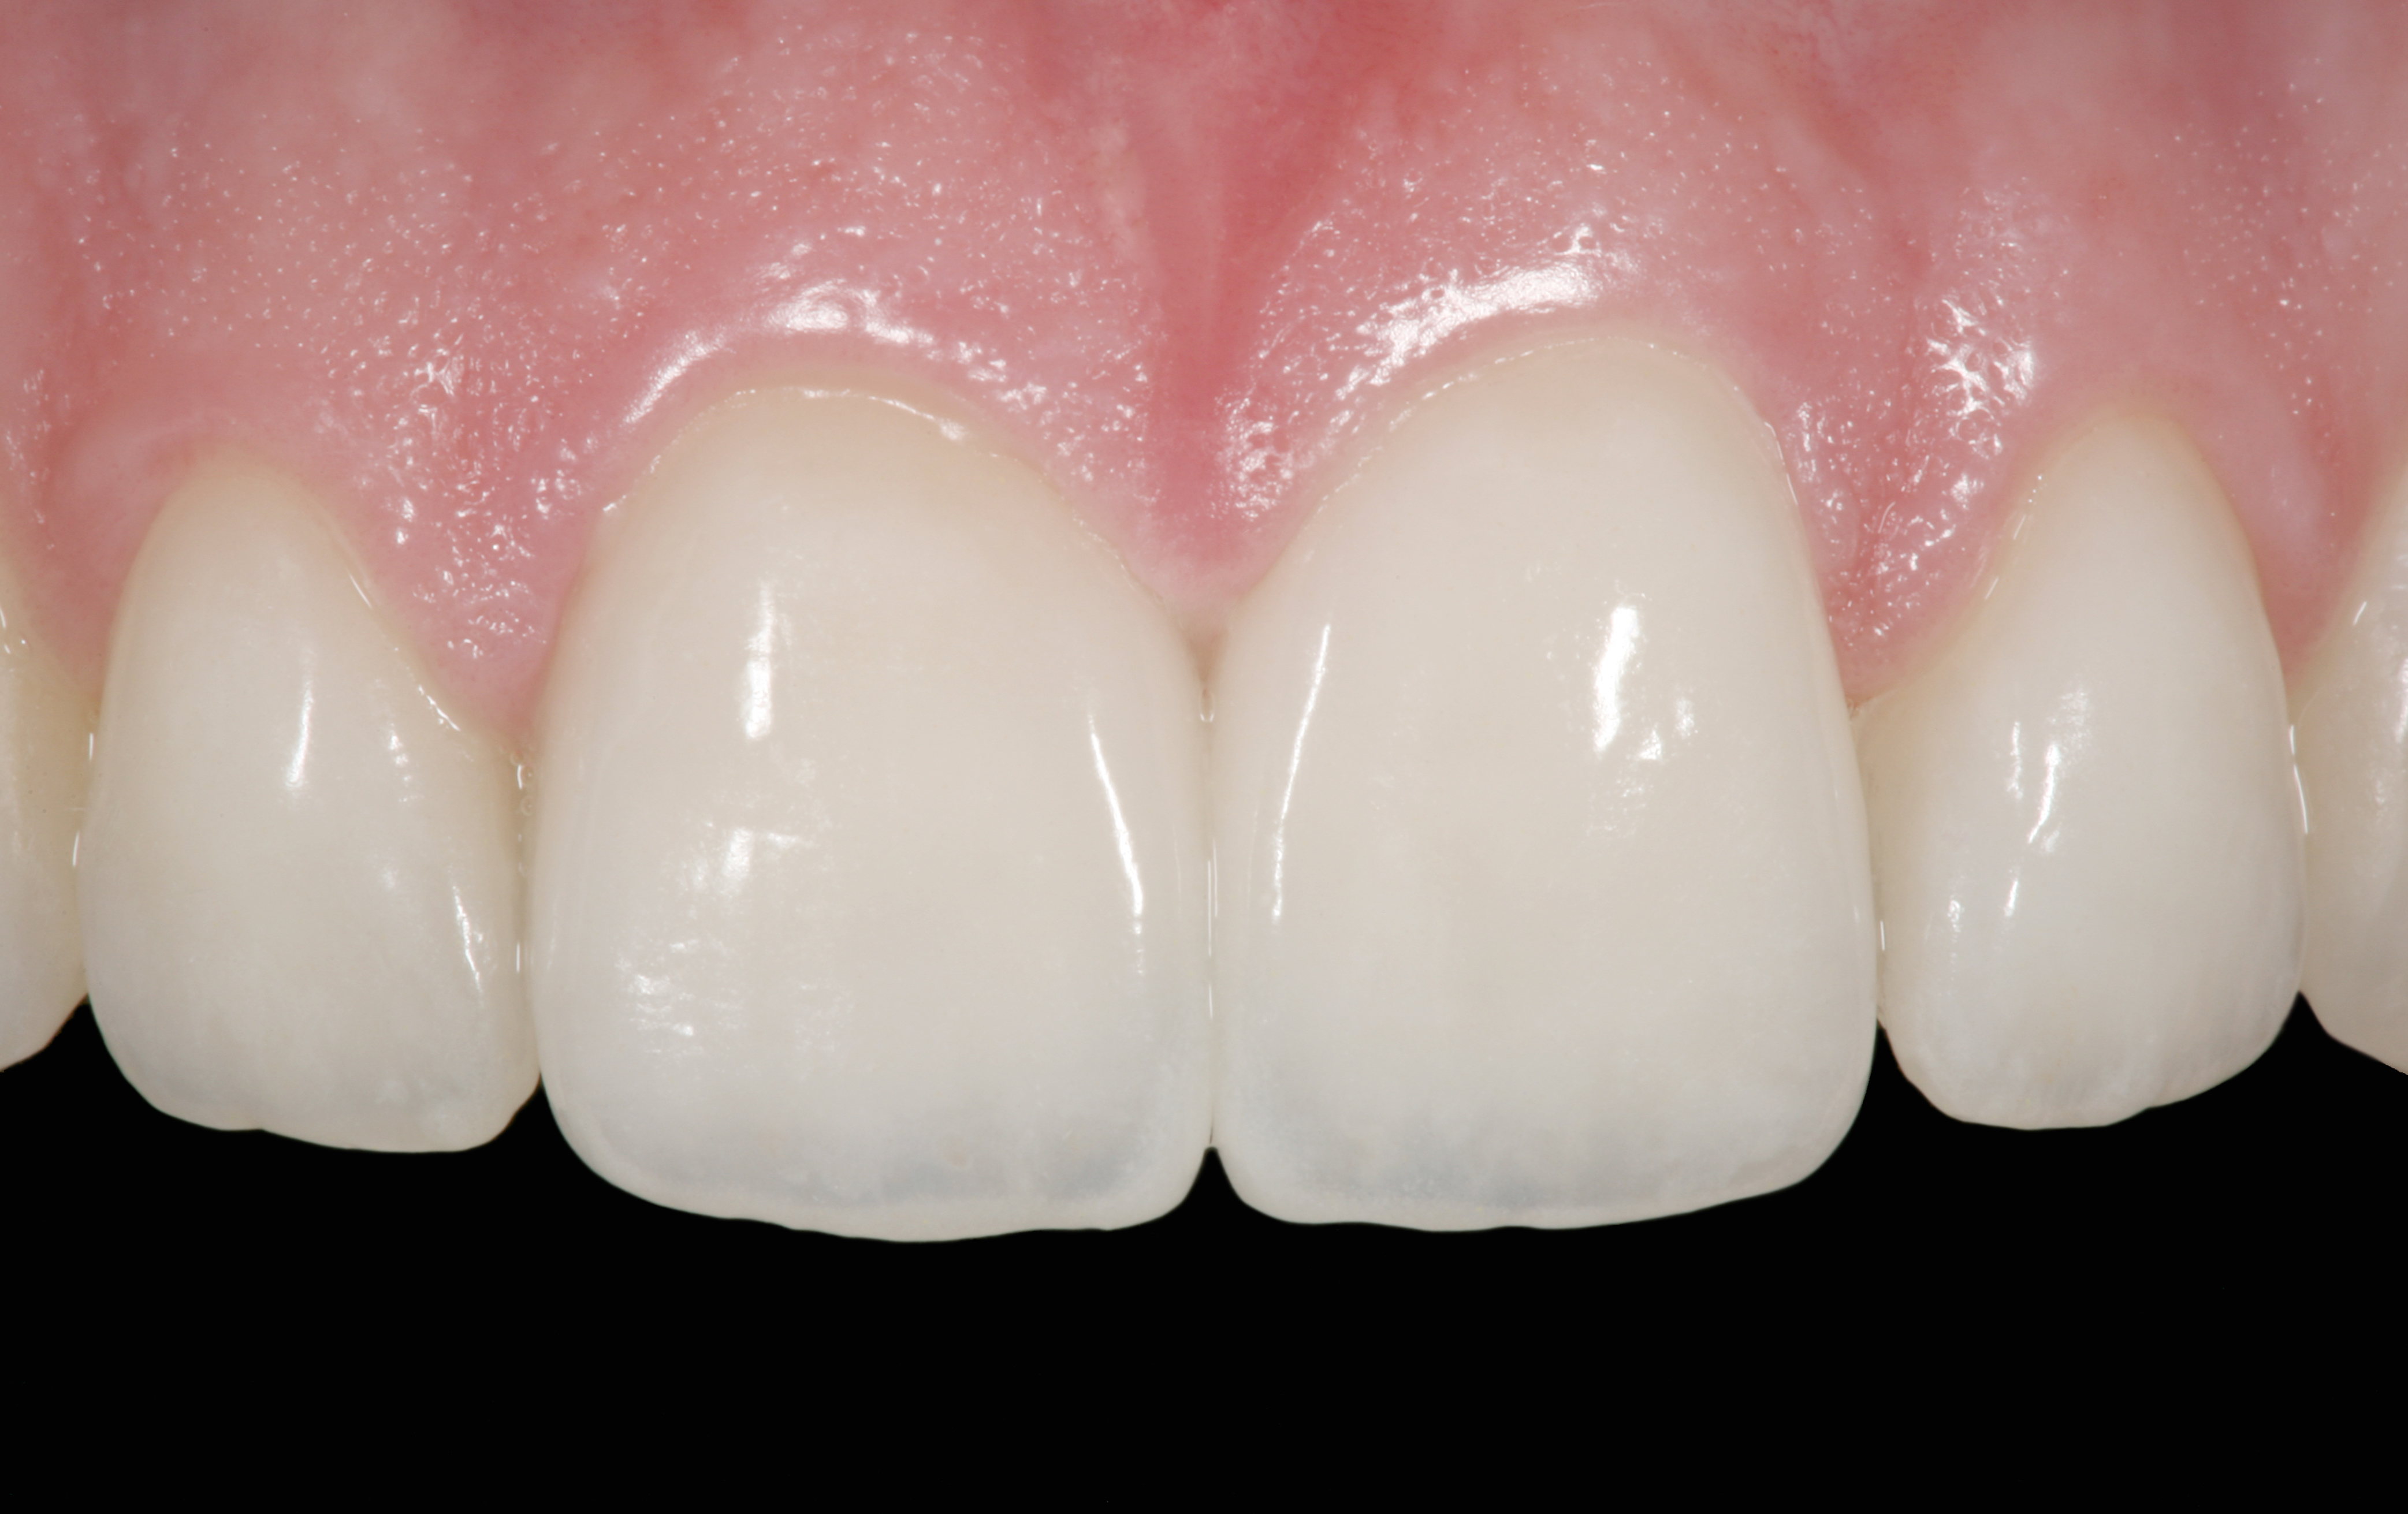

The clinical application of this protocol is illustrated in a patient situation where laminate veneers were placed on four maxillary incisors to replace lost tooth structure and restore function and esthetics. The failing restorations were removed, followed by a conservative veneer preparation (Figure 1 and Figure 2). The bonding surfaces of the feldspathic porcelain veneers were acid-etched with hydrofluoric acid for 2 minutes (Figure 3) and thoroughly rinsed. Then a silane coupling agent was applied (Figure 4). Figure 5 demonstrates the situation after bonding the veneers to the teeth with a composite resin luting agent.

The pretreatment situation.

Figure 1